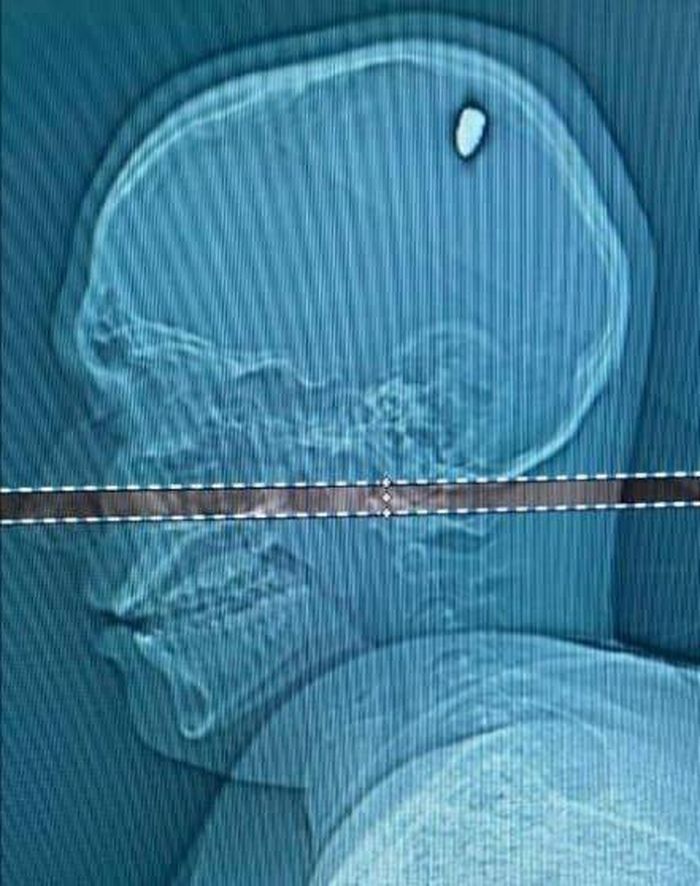

Lo lắng cho sức khỏe, Mateus đã đến một bệnh viện tư nhân địa phương để kiểm tra. Tại đây, anh cũng kể với các bác sĩ chuyện bị ném đá vào đầu trong đêm giao thừa. Khi có kết quả chụp CT, Mateus mới tá hỏa phát hiện viên đá đập vào đầu anh thực chất là một viên đạn 9mm và vẫn đang găm bên trong.

"Các bác sĩ và y tá gần như không thể tin vào mắt mình khi nhìn thấy Mateus vẫn có thể trải qua 4 ngày bình thường không cảm thấy gì sau khi bị bắn vào đầu", mẹ của Mateus nói. "Điều này thật không giải thích được. Con trai tôi như được sinh ra một lần nữa".

Các bác sĩ đã tiến hành phẫu thuật gắp bỏ viên đạn cho Mateus. Hiện anh đang trong quá trình hồi phục hoàn toàn.